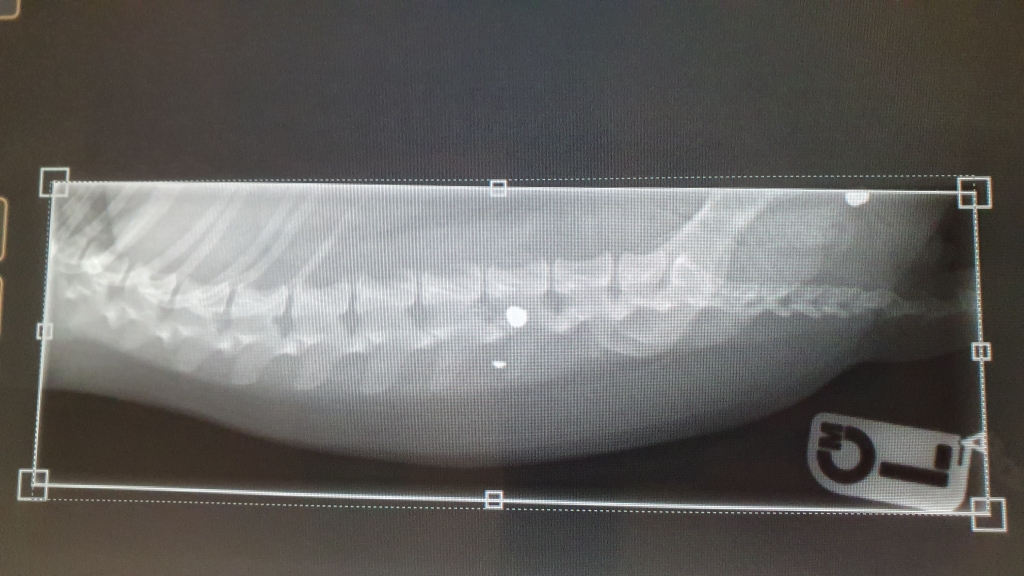

Three-year-old Hunter was examined at West Midlands Referrals (WMR), near Burton on Trent, Staffordshire, where X-rays taken by the Linnaeus-owned practice revealed the dog had been hit by two air gun pellets, one of which was lodged dangerously close to his spine.

“Radiographs were obtained with Hunter under general anaesthesia which revealed two air gun pellets, one close to the base of his tail and, more worryingly, one adjacent to his spine in his lower back.

“The first one was palpable on rectal examination but was mobile and was not near to any important structures, so I judged that it was not concerning and so it was left.

“However, it was absolutely necessary to remove the other pellet, as it was so close to a vital nerve root which was important for the sensory and motor function of Hunter’s corresponding back leg.

“We believed the pellet was already responsible for irritating the nerve as Hunter moved and was causing him significant discomfort, so it needed to come out to avoid any further impact.

“Surgery to safely recover the pellet was challenging, though, because of its proximity to the nerve root and the spine.

“Surgery took around 50 minutes. We had good images of the affected area, so we knew precisely where to locate the pellet. We just needed to take obvious care in removing it safely.